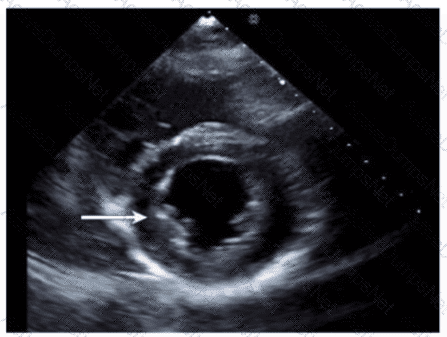

Which wall is indicated by the arrow on this image?